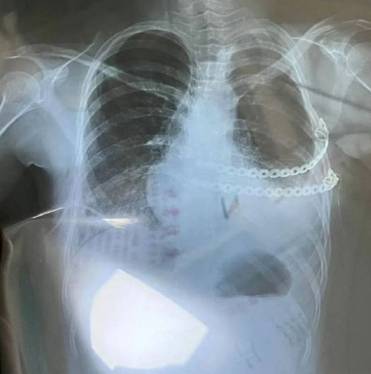

10일(현지시간) 홍콩 사우스차이나모닝포스트에 따르면 쉬안 자이(22)는 희소 질환인 '폴란드 증후군'을 앓고 있다. 이는 한쪽 가슴 혹은 유두가 덜 발달하거나 없는 선천성질환이다.

일부에서는 짧은 물갈퀴 모양의 손가락, 즉 단지증이나 합지증이 동반되는 경우도 있다. 주로 여성보다는 남성에게 약 3배 정도 더 많이 나타나며, 대부분의 경우 신체의 오른쪽에 증상을 보인다.

다만 모든 짝가슴이 폴란드 증후군에 해당하는 것은 아니며, 희귀하고 복잡하지만 치료가 불가능한 것도 아니다. 발생 원인은 태아 발달 시기인 임신 6주 정도에 쇄골하동맥으로 공급되는 혈류의 흐름에 방해를 받아 이들이 공급하는 조직이 저형성되기 때문이라고 알려져 있다.

기대 수명에는 영향을 미치지 않지만, 상태에 따라 호흡 문제와 외모적 자신감이 결여돼 이를 개선하기 위해 재건술을 받기도 한다.

결국 쉬안은 10대 때 가슴 재건 수술을 받았으나 실패했고, 3년간 석고로 만든 코르셋을 착용했다. 그러나 갈비뼈 기형으로 인해 때로는 숨을 쉬기도 힘들었다고.

이후 쉬안은 2022년 기형 교정용 인공 신체를 제작하는 보석 브랜드 운영자를 만나 도움을 요청했다. 그렇게 그는 분홍색과 은색 보석으로 제작된 인공 가슴을 얻을 수 있었다.